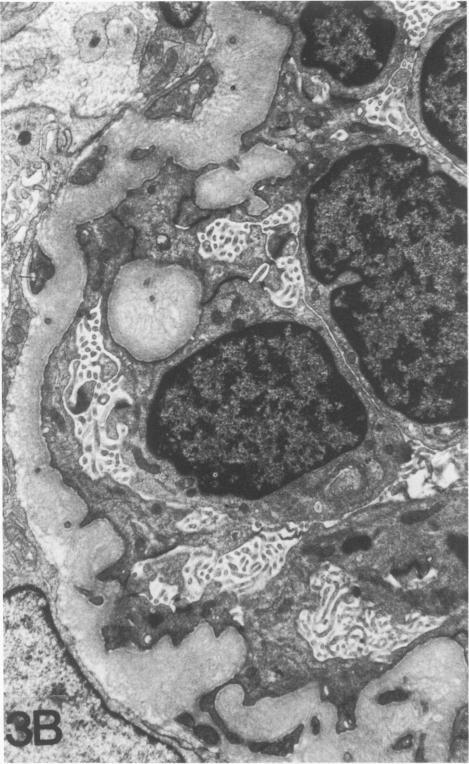

Eight examples of nephroblastoma induced transplacentally in the partially inbred IIIVO/J strain of rabbit by a single intraperitoneal (60 mg/kg) dose of N-ethylnitrosourea (ENU) were studied by transmission electron-microscopy. At the light-microscopic level the ENU-induced tumors displayed the complex array of histotypic components described in a previous report (Hard GC, Fox RR: Histologic characterization of renal tumors (nephroblastomas) induced transplacentally in IIIVO/J and WH/J rabbits by N-ethylnitrosourea. Am J Pathol 1983, 113:8-18) namely, blastema, tubular profiles, "reniform" islands, glomeruloid bodies, squamoid foci, fascicles of mesenchymelike tumor cells, and an increasing fibrocollagenous stroma. Ultrastructurally, blastemalike cells were undifferentiated forms resembling metanephric blastema. Tubular profiles of varying development were typified by very prominent apical junctional complexes and a basal lamina, but no organized brush-border. "Reniform" islands were groups of more maturely formed tubules associated with the production of an interstitial matrix consisting almost solely of multilamellar basement membrane. Glomeruloid bodies were invaginations of small podocytelike cells, with a profusion of thin cytoplasmic processes resembling foot processes, and internal, homogeneous areas of basement membrane continuous with that surrounding the entire structure. As such, these structures were consistent with primitive attempts at glomerular differentiation but without vascular or mesangial elements. The squamoid foci were representative of true squamous differentiation in comprising cells filled with intermediate filaments and interconnected by lateral interdigitations and multiple, well-formed desmosomes. Spindle-shaped tumor cells disposed in fascicles, which could have been interpreted as bipotential differentiation into secondary mesenchyme at the histologic level, differed from the blastemal cell type only in shape. Ultrastructurally, the fascicles, in most cases, consisted of thin, basement-membrane-invested ribbons of attenuated cells enclosing small lumens sealed by intercellular junctions, suggestive of abortive tubule formation. Tumor cells disposed in fascicles therefore conformed to the same epithelial lineage as the other neoplastic components of these tumors. In contrast, cellular elements of the fibrocollagenous stroma--namely, fibroblasts, vascular endothelial cells, and scattered mononuclear inflammatory cells--could be clearly discriminated from the various tumor cell components on morphologic grounds, constituting a host reaction.(ABSTRACT TRUNCATED AT 400 WORDS)

通过腹腔注射单次剂量(60毫克/千克)的N-乙基亚硝脲(ENU),在部分近交系IIIVO/J兔中经胎盘诱导产生了8例肾母细胞瘤,采用透射电子显微镜对其进行了研究。在光学显微镜水平上,ENU诱导的肿瘤呈现出先前报告中所描述的复杂组织学成分组合(Hard GC,Fox RR:N-乙基亚硝脲经胎盘诱导IIIVO/J和WH/J兔产生的肾肿瘤(肾母细胞瘤)的组织学特征。《美国病理学杂志》1983年,113:8 - 18),即胚基、管状结构、“肾形”岛、肾小球样体、鳞状病灶、间充质样肿瘤细胞束以及逐渐增多的纤维胶原基质。超微结构上,胚基样细胞是未分化的形式,类似于后肾胚基。不同发育阶段的管状结构以非常突出的顶端连接复合体和基底膜为特征,但没有有组织的刷状缘。“肾形”岛是一组形成更成熟一些的小管,伴有几乎仅由多层基底膜组成的间质基质的产生。肾小球样体是小足细胞样细胞的内陷,有大量类似于足突的细细胞质突起,以及内部均匀的基底膜区域,与围绕整个结构的基底膜连续。因此,这些结构与肾小球分化的原始尝试一致,但没有血管或系膜成分。鳞状病灶代表真正的鳞状分化,其细胞充满中间丝,通过侧向交错和多个形成良好的桥粒相互连接。排列成束的梭形肿瘤细胞,在组织学水平上可被解释为双潜能分化为次级间充质,与胚基细胞类型仅在形状上有所不同。超微结构上,在大多数情况下,这些束由包裹着小腔隙的、基底膜包绕的、变薄细胞的细带组成,小腔隙由细胞间连接封闭,提示小管形成失败。因此,排列成束的肿瘤细胞与这些肿瘤的其他肿瘤成分属于相同的上皮谱系。相比之下,纤维胶原基质的细胞成分,即成纤维细胞、血管内皮细胞和散在的单核炎性细胞,在形态学上可与各种肿瘤细胞成分清楚地区分开来,构成宿主反应。(摘要截选至400字)